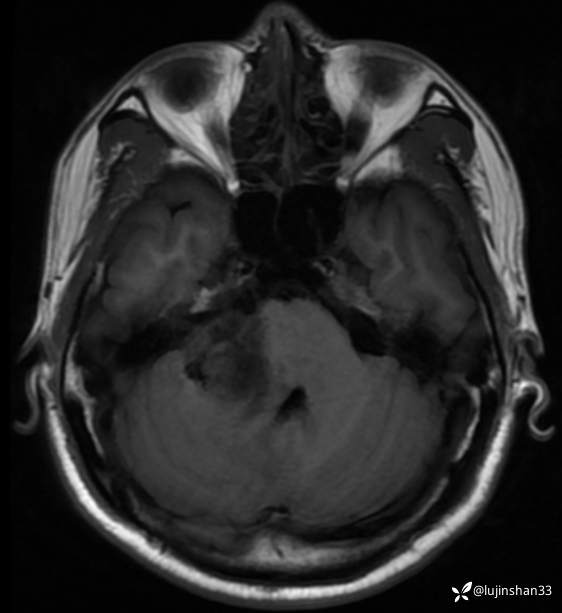

术前CT及MRI